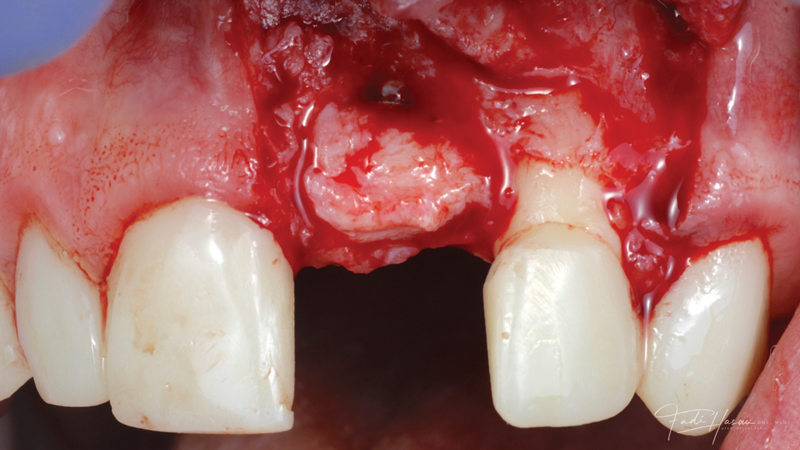

(12.) Flap reflection to assess the position of the coronal aspect of the implant and facilitate soft-tissue grafting.

Figure 12

A patient presented for the restoration of an implant that had been placed at the site of tooth No. 9, which exhibited a residual soft-tissue deficiency and an undulating facial soft-tissue morphology (Figure 11). The objective of the treatment was to change the appearance and thickness of the facial soft tissue prior to crown placement to optimize the esthetics and prevent future soft-tissue dehiscence. After flap reflection (Figure 12), a graft was acquired from the patient's tuberosity to augment the supracrestal soft tissue (Figure 13). A volume-stable collagen matrix was then placed to further increase the thickness of the soft tissue adjacent to the implant body (Figure 14), and the flap was sutured closed (Figure 15). Following a 3-month healing period, a positive change in the soft tissue's morphology was apparent; however, its volume remained deficient when compared with that of tooth No. 8 (Figure 16). When the screw-retained crown was delivered, a second graft was acquired from the tuberosity and placed to further increase the volume of the supracrestal soft tissue (Figure 17 and Figure 18). A postoperative healing period of 4 months resulted in an ideal position of the margin of tooth No. 9 with regard to its contralateral counterpart as well as more natural looking soft-tissue morphology and excellent supracrestal soft-tissue thickness (Figure 19 and Figure 20). Eight months postoperatively, the position of the gingival margin and the thickness of the soft tissue had been maintained (Figure 21 and Figure 22).